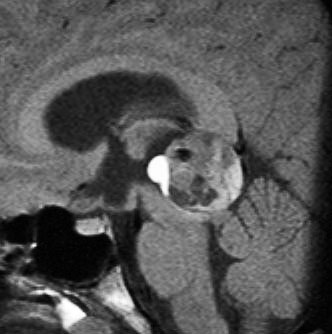

成人男性の松果体芽腫です。左のCTでは白く見える石灰化があります。水頭症があって頭痛と嘔吐で発症しました。右のMRIでは腫瘍の形が丸くなくて周囲の脳に浸潤したり脳室の壁などにべっとり広がっているように見えます。悪性腫瘍の特徴的な像で,開頭手術をしても摘出できないことが判ります。松果体芽腫は悪性度が高くて(WHOグレード4),脊髄などに播種転移したりしますし,手術だけでは治りません。

腫瘍は定位脳手術で生検をしました。水頭症に対しては内視鏡で第3脳室開窓術を行なって症状を改善しました。左のMRIで水頭症が良くなっているのが判ると思います。それから,全脳脊髄に30グレイの放射線治療をして腫瘍局所には24グレイの照射を追加しました。同時にICE化学療法というのを6コースしました。右のMRIでは治療が終わって小さく固まった残存腫瘍が見えます。この残存腫瘍は第3脳室の壁にくっついていて摘出するリスクがとても高いと思いましたので,そのままずーっと10年間様子を見ていますが再発していません。でも,残存腫瘍がなんとか取れる時は徹底的に取ってしまった方が再発率は少ないといえます。